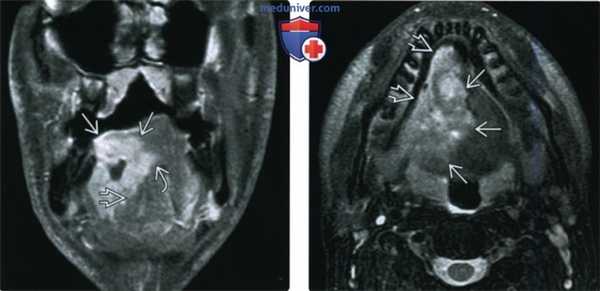

(Слева) На изображении показан ПКР альвеолярного гребня нижней челюсти с распространением на тело нижней челюсти (Т4а). Обратите внимание на инвазию нижнего альвеолярного нерва - момент, важный для полной резекции опухоли.

(Справа) При аксиальной КУ с КУ визуализируется объемное образование неоднородной структуры, разрушающее тело нижней челюсти слева. Опухоль распространяется кнаружи между десной и щекой, прорастая в щеку, а также кнутри, прорастая в дно полости рта. Опухоль (T4aN1) была полностью удалена, дефект тканей закрыт комбинированным лоскутом. (Слева) На фото у мужчины 66 лет виден патологический очаг В неправильной формы с уплотнением и изъязвлением тканей в области альвеолярного гребня верхней челюсти, начинающийся на уровне первого премоляра. Была выполнена биопсия, подтвердился инвазивный плоскоклеточный рак. Клинически стадия была определена как T2N0.

(Справа) При МРТ Т1ВИ в аксиальной проекции у этого же пациента определяется мягкотканный компонент снаружи от альвеол нижней челюсти; жировая ткань (по сравнению с противоположной стороной) отсутствует. На томограммах не определяется убедительных признаков инфильтрации костного мозга, что позволяет выполнить частичную максиллэктомию.